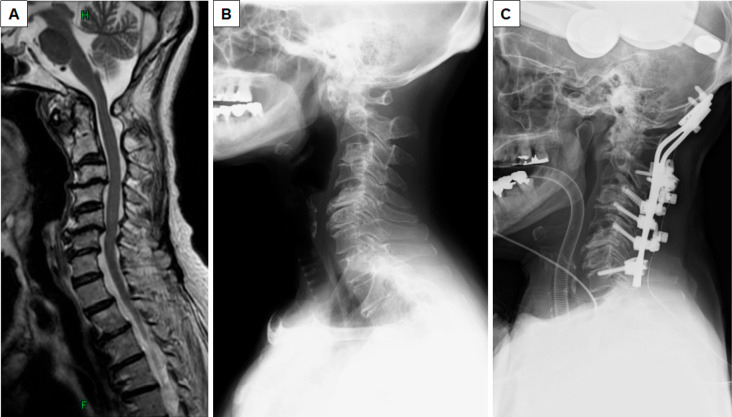

Abstract Image